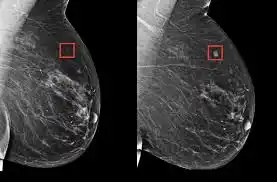

La inteligencia artificial (IA) es capaz de identificar a las mujeres con un riesgo elevado de cáncer de mama varios años antes de que se diagnostique, informó el martes el Instituto noruego de salud pública (FHI).

Cinco investigadores del FHI, junto con especialistas de la Universidad de California y de la Universidad de Washington, utilizaron un algoritmo de IA comercialmente disponible para analizar retrospectivamente las mamografías de 116.495 mujeres que participaron en un programa de detección en Noruega entre 2004 y 2018.

A través de un sistema de puntuación de riesgos basado en las mamografías, el algoritmo pudo predecir un riesgo elevado de cáncer de mama, e incluso determinar qué mama estaba en riesgo, entre cuatro y seis años antes del diagnóstico.

«Observamos que la mama que desarrollaba el cáncer obtenía un puntaje de IA aproximadamente dos veces más alto que la otra», explicó Solveig Hofvind, responsable del proyecto y directora del programa de detección, citada en un comunicado.